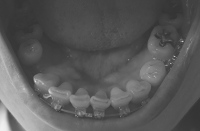

奥に引っ張るのは前歯の隙間を詰めてからにするとかなんとか言い出して、ワイヤー交換して前の歯にパワーチェーン(だと思う)を付けて終了。

しかもワイヤーをもう一段太くしようとして、ブラケットに無理やり押し込んで抜けなくなり、顎をギシギシいわせながらぐいぐい引っ張られました。以前にも同じことやってんのよね、この先生。

その後、何事もなかったようにワイヤーを付け始めたので抜けたのか?と思っていたのですが、終わってから見てみたら、刺さったワイヤーはそのままで、交換したワイヤーがブラケットに細い針金で固定されてました

んでまた「次回から後ろに下げていきます」、だって! 何回目だよそのセリフ。

まぁ、今まではいろいろ引き伸ばされる原因もあったけど、今回のは明らかにヤル気がなかっただけと違う? だいだい次回から引っ張っていくんなら、奥のブラケットは付け直しておくべきと違う? ワイヤーさすとこが埋まってしまってるんやから、また付け直さなあかんのと違うの? そしたら次回また引っ張ったりできひんのと違うの?

まぁほんまに、ないんやろうけどなぁ。奥に引っ張るのは前歯の隙間を詰めてからにするとかなんとか言い出して、ワイヤー交換して前の歯にパワーチェーン(だと思う)を付けて終了。